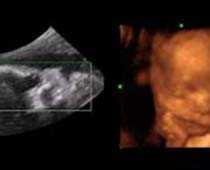

Clips vidéo 4D scan ultrason fœtal | Dr N Layyous

Clips vidéo 4D scan ultrason fœtal